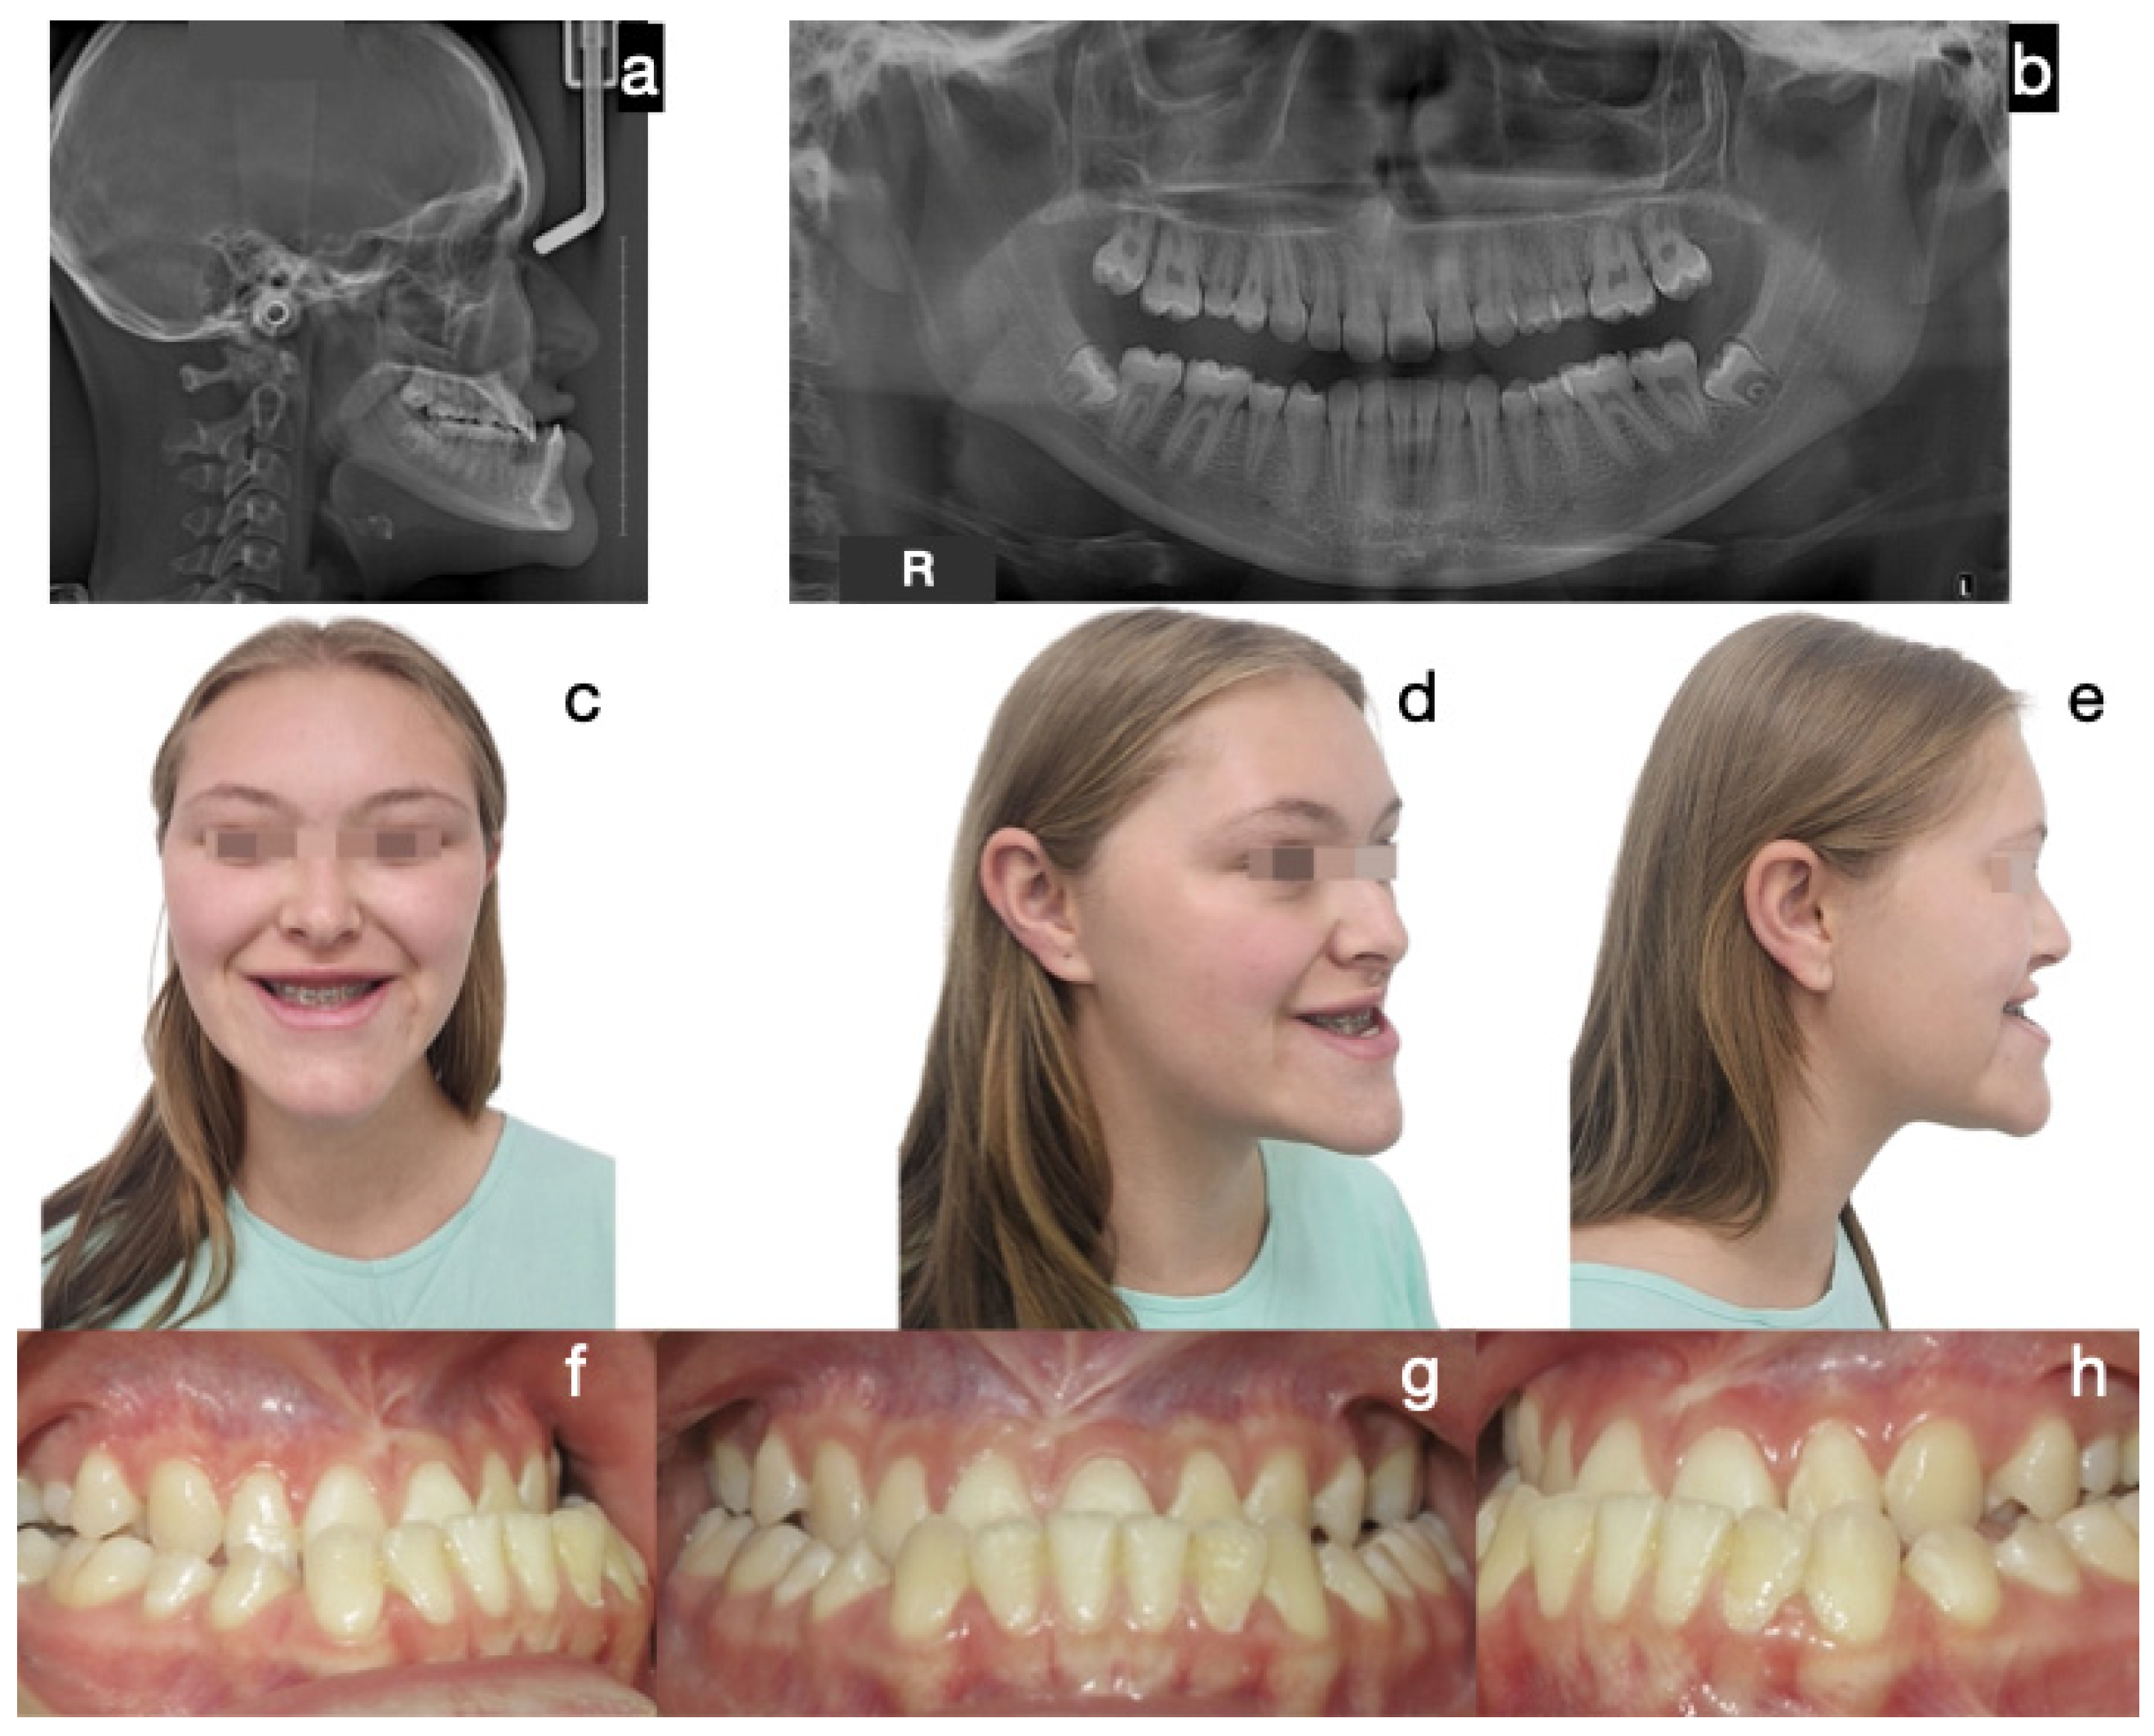

Figure 2. Case 1 corresponds to patient 1, described in Table 1. Protocol A (bilateral condylectomy and orthognathic surgery in two surgical stages): initial photos. The severity of the Class III skeletal and dental discrepancy with negative overjet of −12 mm and concave profile is evidenced. (a) Lateral skull radiograph, (b) panoramic radiograph, (c) frontal extraoral photograph, (d) ¾ extraoral photograph, (e) lateral extraoral photograph, (f) right lateral intraoral photograph, (g) frontal intraoral photograph, (h) left lateral intraoral photograph.

The most common treatment approach was Protocol A (cases 1, 3, 6, 7, and 10), characterized by bilateral condylectomy, to stop the aggressive growth, then orthodontic therapy to prepare the patient for a second surgical intervention to correct the sequel according to the patient’s alterations. One of the patients who followed this protocol is the one presented in Figure 2, Figure 3 and Figure 4, which shows a 14-year-old female patient (Case 1, Table 1), with severe mandibular prognathism, that was accentuated after menarche with no family history of Class III. Anatomically, as evidenced by the radiographic images, the condyles are elongated but have normal anatomy. During the diagnostic process, a nuclear medicine test was conducted to obtain the radiopharmaceutical uptake in the condyles concerning the clivus, and the result was 1.4 for each condyle, confirming the active state of CH. With this diagnosis, it was decided to proceed with a first surgical intervention consisting of a 6 mm bilateral high condylectomy. The results of the histopathological test reported a soft condyle thickness of 0.6 mm for the right condyle and 0.7 mm for the left condyle, with positive findings for BCH. After surgery, orthodontic decompensation was performed for 12 months, and a second surgical intervention was scheduled, this time, bimaxillary to correct the skeletal alteration. Post-surgical orthodontics were then carried out for 8 months to achieve adequate occlusal stability.